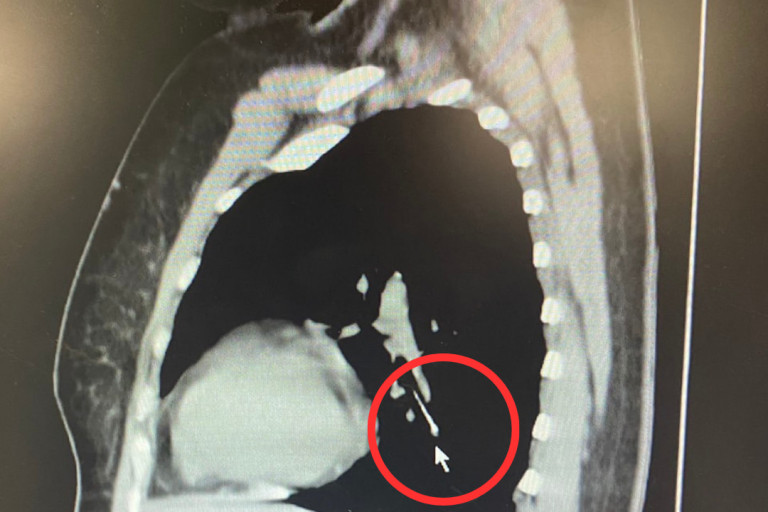

ผู้ป่วยหญิงอายุ 49 ปี ขณะเย็บผ้า ได้คาบเข็มหมุดไว้ในปาก ต่อมามีอาการสำลักเข็มหมุดหลุดลงคอ จึงได้มาตรวจที่ โรงพยาบาลนครพิงค์ ทำการตรวจเอ็กซเรย์คอมพิวเตอร์ พบว่าเข็มหมุดหลุดลงไปคาอยู่ในหลอดลมปอดข้างซ้าย